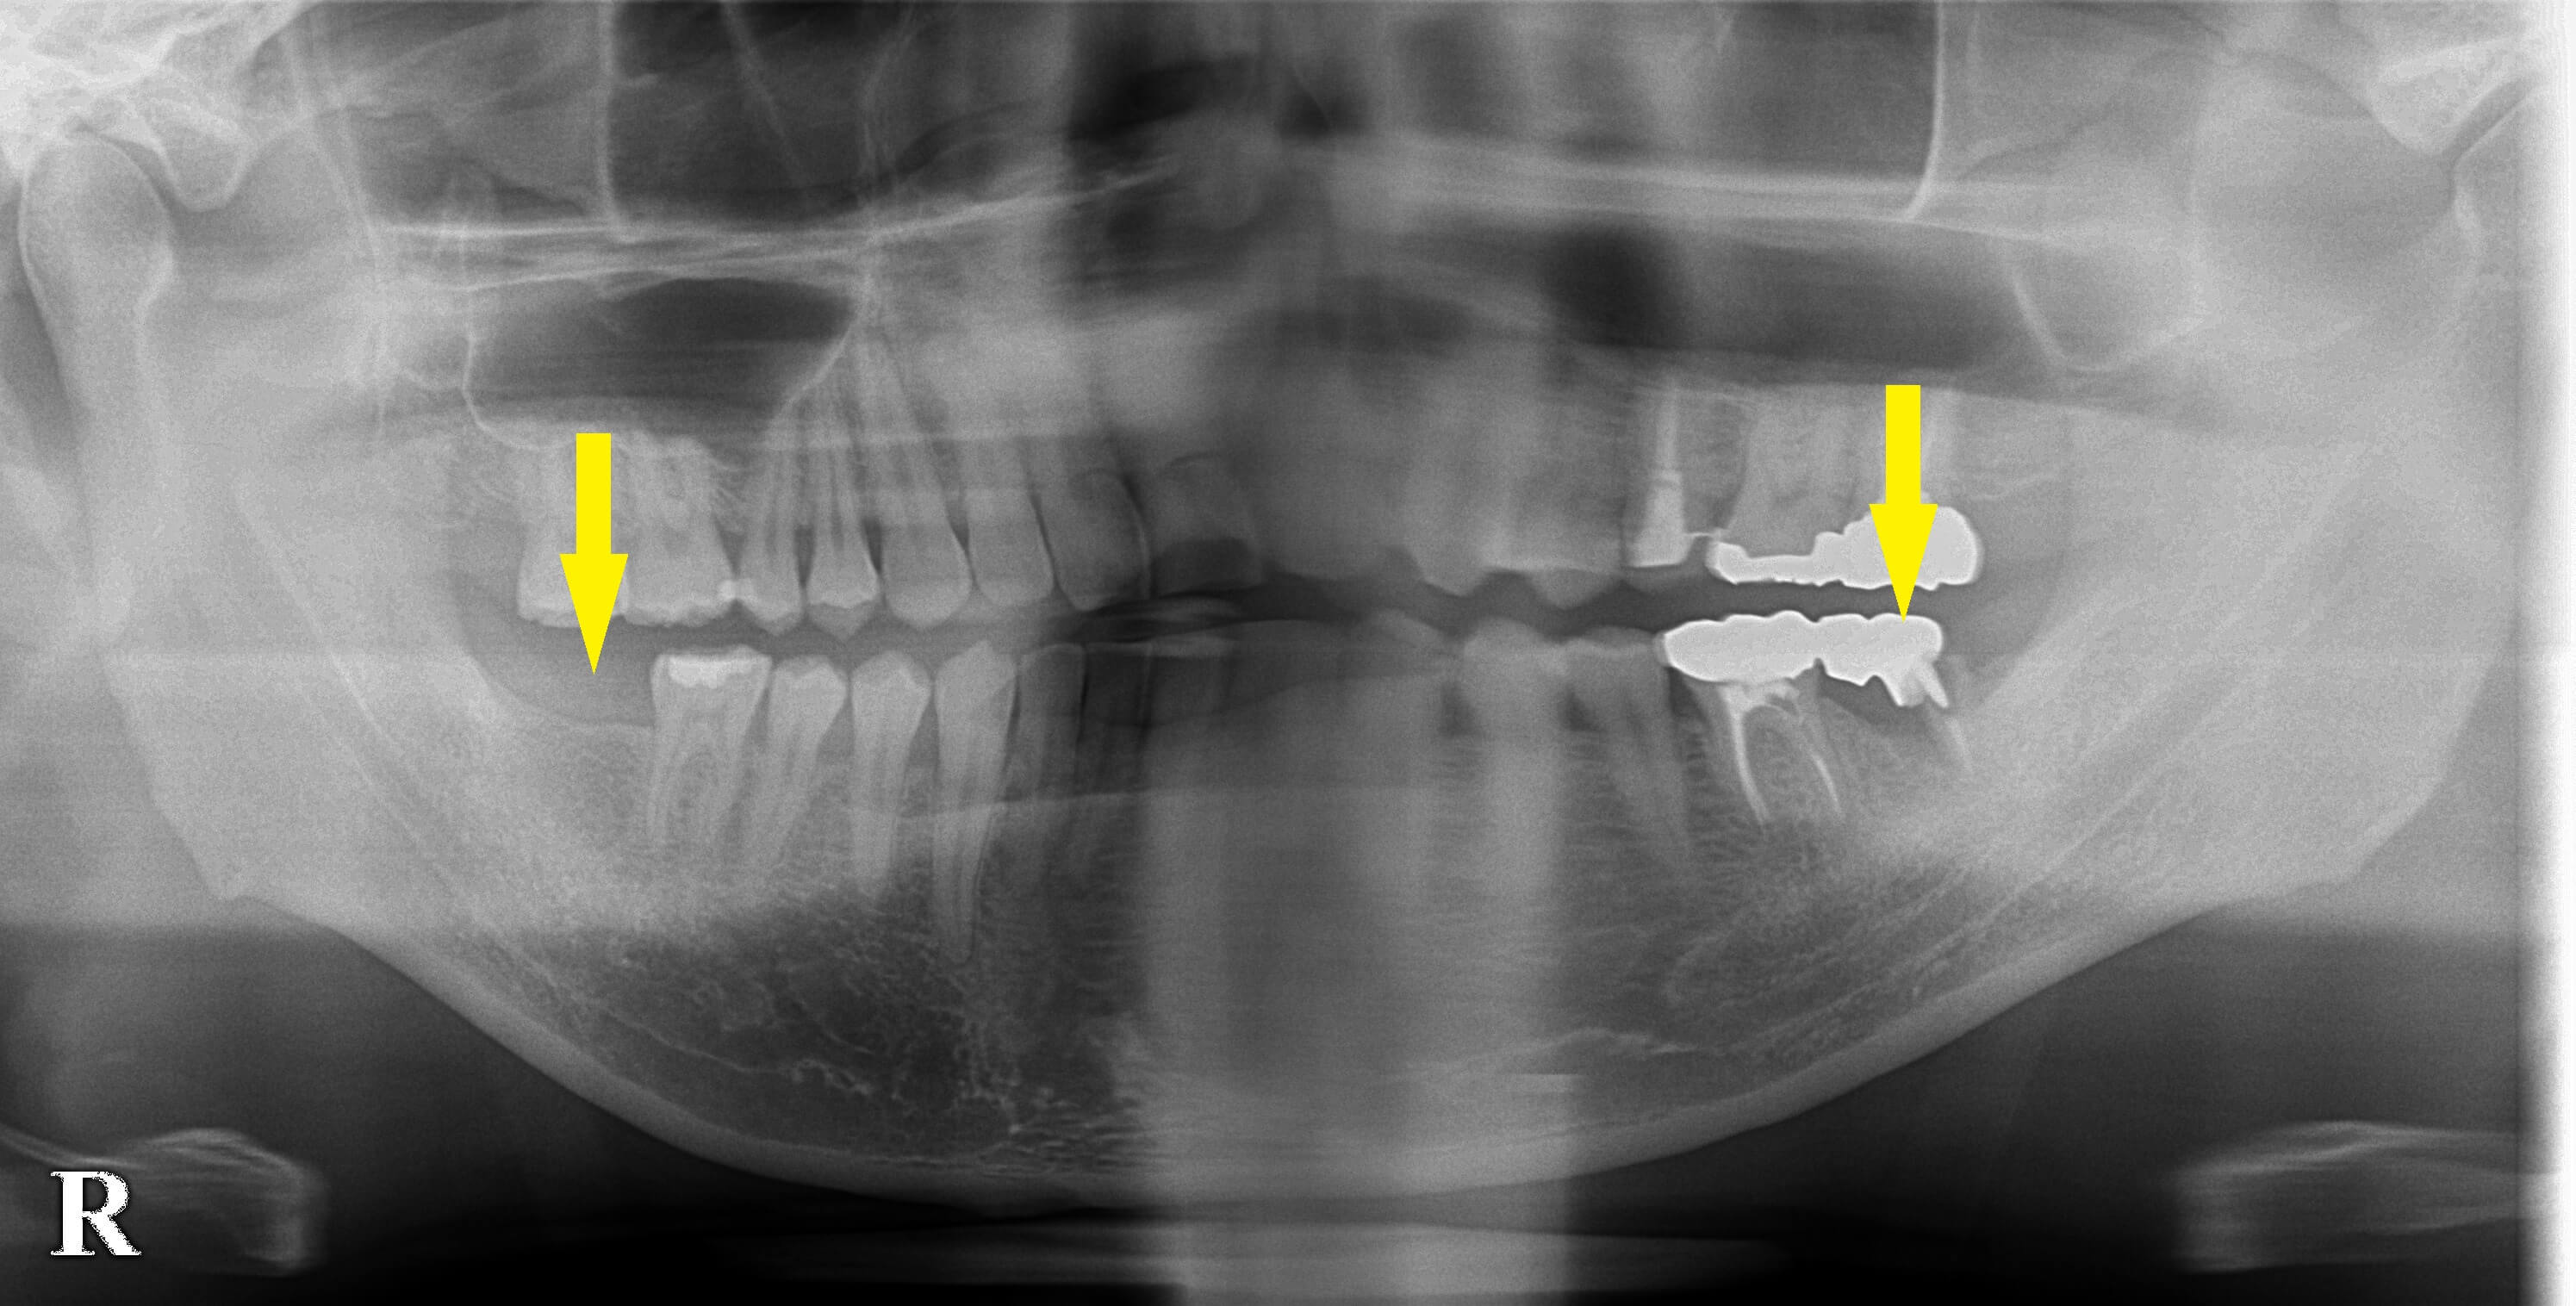

下顎両側の大臼歯のインプラント治療を希望されて来院されました。

右下顎第二大臼歯は数年前に抜歯しそのまま過ごされていたそうです。

左下顎第二大臼歯は最近になって、腫れ痛みを自覚するようになったそうです。

左側の方は抜歯、治癒を待って、インプラント埋入予定としました。

右側は骨量に問題ありませんでしたので、本日インプラント埋入術を行いました。